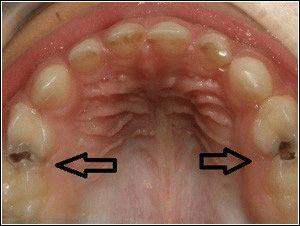

Carii se poate dezvolta la orice persoană, la orice vârstă. Cauza principală a cariei este un proces inflamator cauzat de bacterii care se găsesc în placa dentară și resturile alimentare. Alimentația necorespunzătoare, stresul, neglijarea normelor de igienă pot accelera semnificativ procesul carios. De asemenea, importante sunt caracteristicile genetice ale dinților umani, de exemplu, unii oameni au dinți puternici, în timp ce altele sunt dotate cu dinți slabi smalț, care poate fi ușor supus unei înmuiere.

Pentru a vă păstra propriii dinți într-o stare activă din punct de vedere funcțional pentru cea mai lungă perioadă posibilă, este necesar să tratați cariile la timp și în mod corect. Răspunsul la întrebarea: "Cum să tratăm cariile dentare?" Este redusă nu numai la umplerea dinților. Pentru a trata în mod corespunzător cariilor dentare, este necesar, în caz de cea mai mică suspiciune sau disconfort cuplat cu disconfort la nivelul dinților contactați imediat medicul dentist. Mai devreme, prinși caria, cu atât este mai ușor să se vindece, cu atât mai puțin va fi sigiliul în cele din urmă.

Chiar dacă există deja un sigiliu în dinte, acest lucru nu garantează faptul că dintele nu va fi supus procesului carious mai mult. De asemenea, acesta nu este un motiv pentru a crede că este imposibil să faceți ceva și singura cale de ieșire este eliminarea dintelui. Dintele poate fi sigilat în mai multe locuri, dacă cariile se dezvoltă lângă sigiliul existent, medicul dentist poate elimina sigiliul vechi, poate lărgi cavitatea și poate instala un altul mai mare. Amintiți-vă că tratamentul cariilor este mult mai benefic pe termen lung decât îndepărtarea dintelui sau părăsirea procesului patologic pe cont propriu.

Dacă umplutura are un gol, masele de alimente se pot scurge sub ea, apoi cariile se dezvoltă sub sigiliu. Prin urmare, dacă există sub formă de disconfort sub sigiliu, consultați imediat un medic. În acest caz, pentru tratamentul cu succes a cariei, este necesară îndepărtarea umplerii, curățarea cavității și instalarea unui nou.